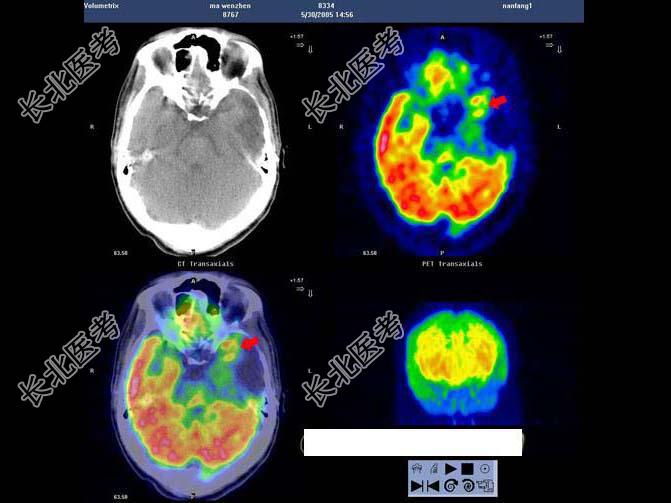

- 多项选择题男,32岁, 确诊左颞叶胶质母细胞瘤Ⅳ级,手术切除病灶, 术后放疗2个月,化疗3个疗程; 现距放疗结束17个月。查体:右上肢轻度乏力, 骶尾部及双足麻木,排便困难; 检查:MRI示左颞叶肿瘤局部复发可能。行PET/CT显像全身检查如图。最可能的诊断是 ( )

A、马尾种植性转移灶

B、恶性肿瘤沿椎管种植性转移

C、左侧颞叶术后瘢痕组织改变

D、左侧颞叶肿瘤复发